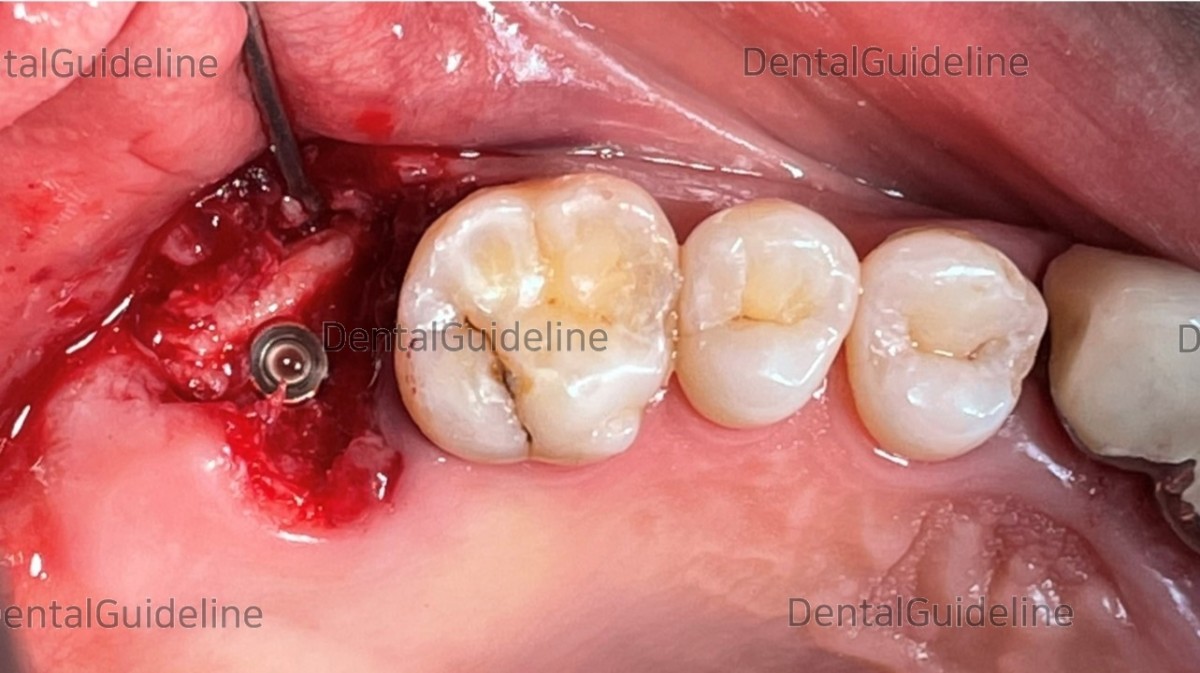

- Osteotomy (serial drilling but under-drilling).

- Arum Implant NB1 Ø5.0*L11.5mm.

- fixture placement.

- Check the initial stability (50Ncm).